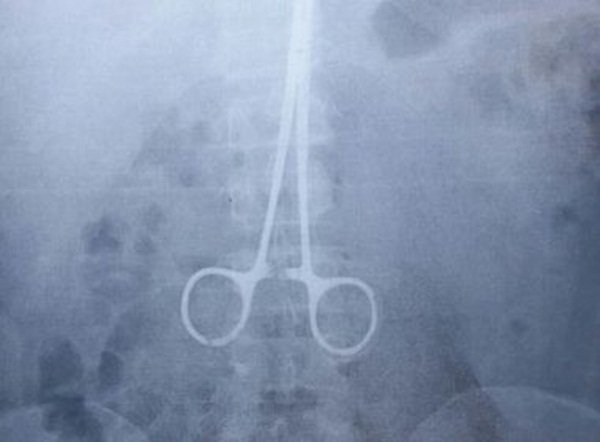

Um morador da cidade de Juiz de Fora, em Minas Gerais, descobriu uma pinça cirúrgica que estava dentro de seu abdômen.

Segundo informações do G1, o objeto teria sido esquecido no corpo há cerca de 15 anos, Ivanildo de Oliveira passou por uma cirurgia na barriga. A descoberta foi feita por meio de uma radiografia feita em razão de uma suspeita de inflamação no apêndice. A pinça tem aproximadamente 16 centímetros de comprimento e foi retirada durante a última quarta-feira (4), no mesmo dia que o objeto foi encontrado.

O procedimento que teria deixado a pinça dentro do abdome aconteceu em 2002, depois que Ivanildo foi esfaqueado durante um assalto. “Na época, passei por uma cirurgia e, como a facada não perfurou nenhum órgão, fui medicado e liberado. Nunca senti nenhuma dor, então nem imaginava que uma pinça poderia ter sido esquecida dentro de mim”, contou Ivanildo em entrevista ao MGTV.